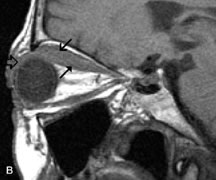

Pleomorphic adenomas demonstrate long T1 and T2 signal characteristics. They may show heterogeneity on T2-weighted images74 and moderate to marked enhancement with contrast.75 Signal characteristics of adenoid cystic carcinoma include hypointensity to fat on T1-weighted images, hyperintensity to fat with increased T2 weighting, and isointensity to fat on proton density-weighted studies (Fig. 23).31,75 Secondary bony alterations of the lacrimal fossa associated with lacrimal gland tumors, such as remodeling (benign mixed tumor) or destruction (adenoid cystic carcinoma), are seen indirectly on MR images; however, bone windows on CT scans provide better delineation of these changes. In contrast to the round or globular appearance of benign or malignant epithelial tumors of the lacrimal gland, lymphoproliferative tumors usually appear to be molding or draping onto the globe and the surrounding bony orbit.

Fig. 23. A. T2-weighted and (B and C) postcontrast fat-suppressed T1-weighted MR scans demonstrate an infiltrative lacrimal region mass than invades the lateral rectus muscle (arrows). This highly cellular lesion is seen to have a very hypointense appearance on the T2-weighted scan.